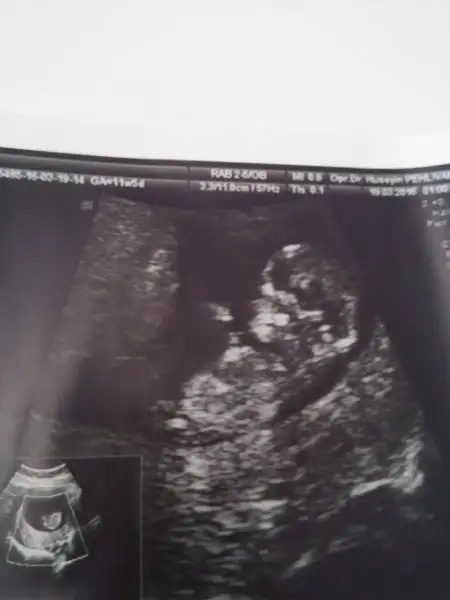

kizlar ilki 9 haftalik ikincisi 10 haftalik fotografi :)) sizce hala erkek mi dusunceniz :))

hala erkek mi dusunceniz? 10+2 gunluguz :))